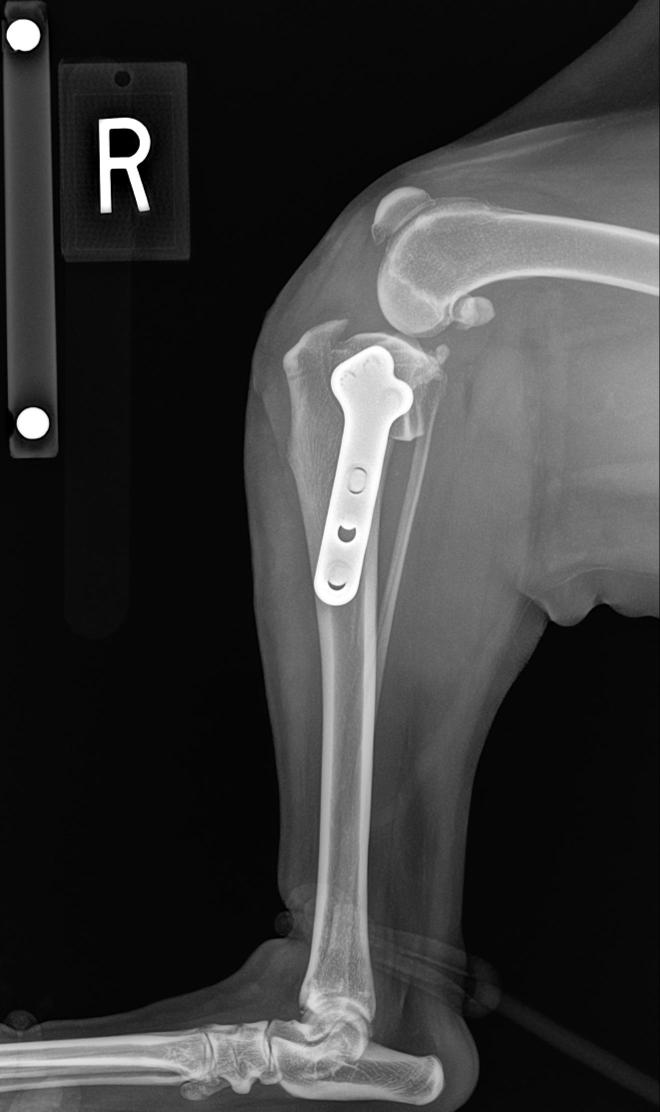

1. Tibial Plateau Leveling Osteotomy (TPLO) – This procedure is a very common procedure that addresses the tibial plateau angle (TPA) or incline/slope of the tibia (refer to previous blog). With this procedure a circular cut is made under the joint in the tibia. Based on a calculation the top of the tibia is rotated to make the top of the tibia relatively flat. This relieves the tension and forward directed force from the ruptured TPLO. This is done in both partial or complete tears to the ACL. After the top of the tibia is rotated a plate and screws are placed on and in the bone. This is a widely used procedure that is typically very successful in returning the patient to near normal function.

2. Tibial Tuberosity Advancement (TTA) – This procedure is also a “bone-cutting” procedure but the osteotomy is not directly under the joint. It is in an area called the tibial tuberosity and is directed vertically (see picture). The idea is to alter the angle that the patellar ligament inserts on the tibial tuberosity to alter the amount of force the quadriceps exert on the stifle and eleviate the forward motion of the tibia. This also, is a successful procedure for stabilization of the knee joint for the partial and complete ACL tear.